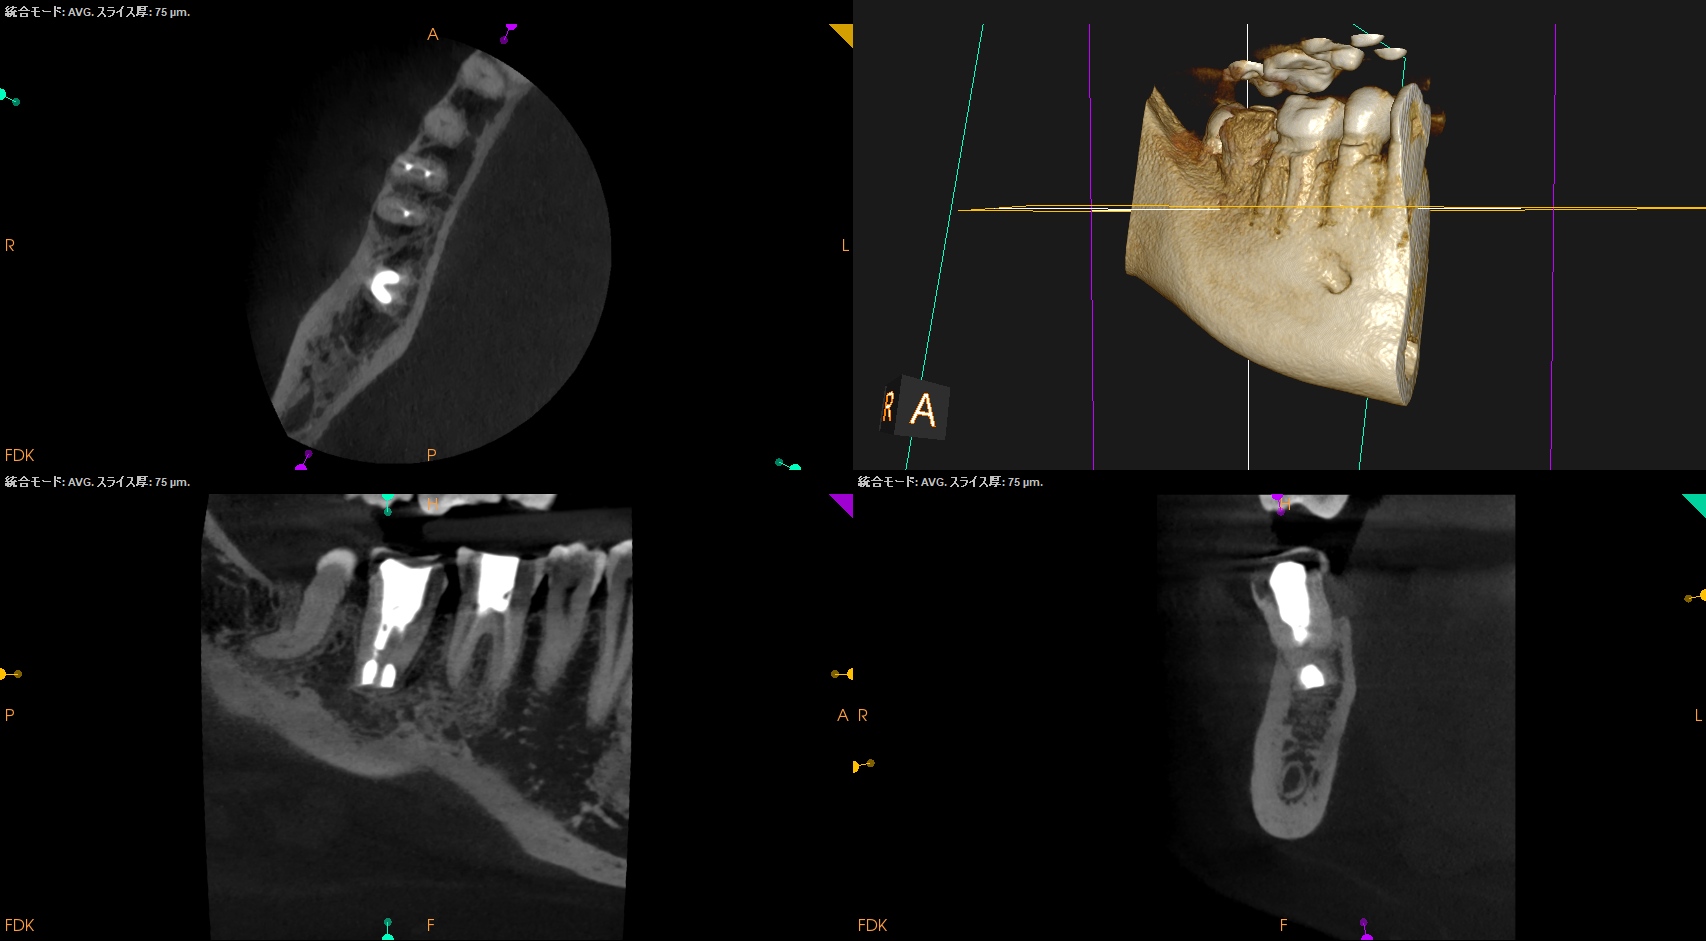

#31 Intentional Replantation 1yr recall(2025.11.28)

ML

MB

D

初診時と比較した。

劇的に治癒していることがわかる。